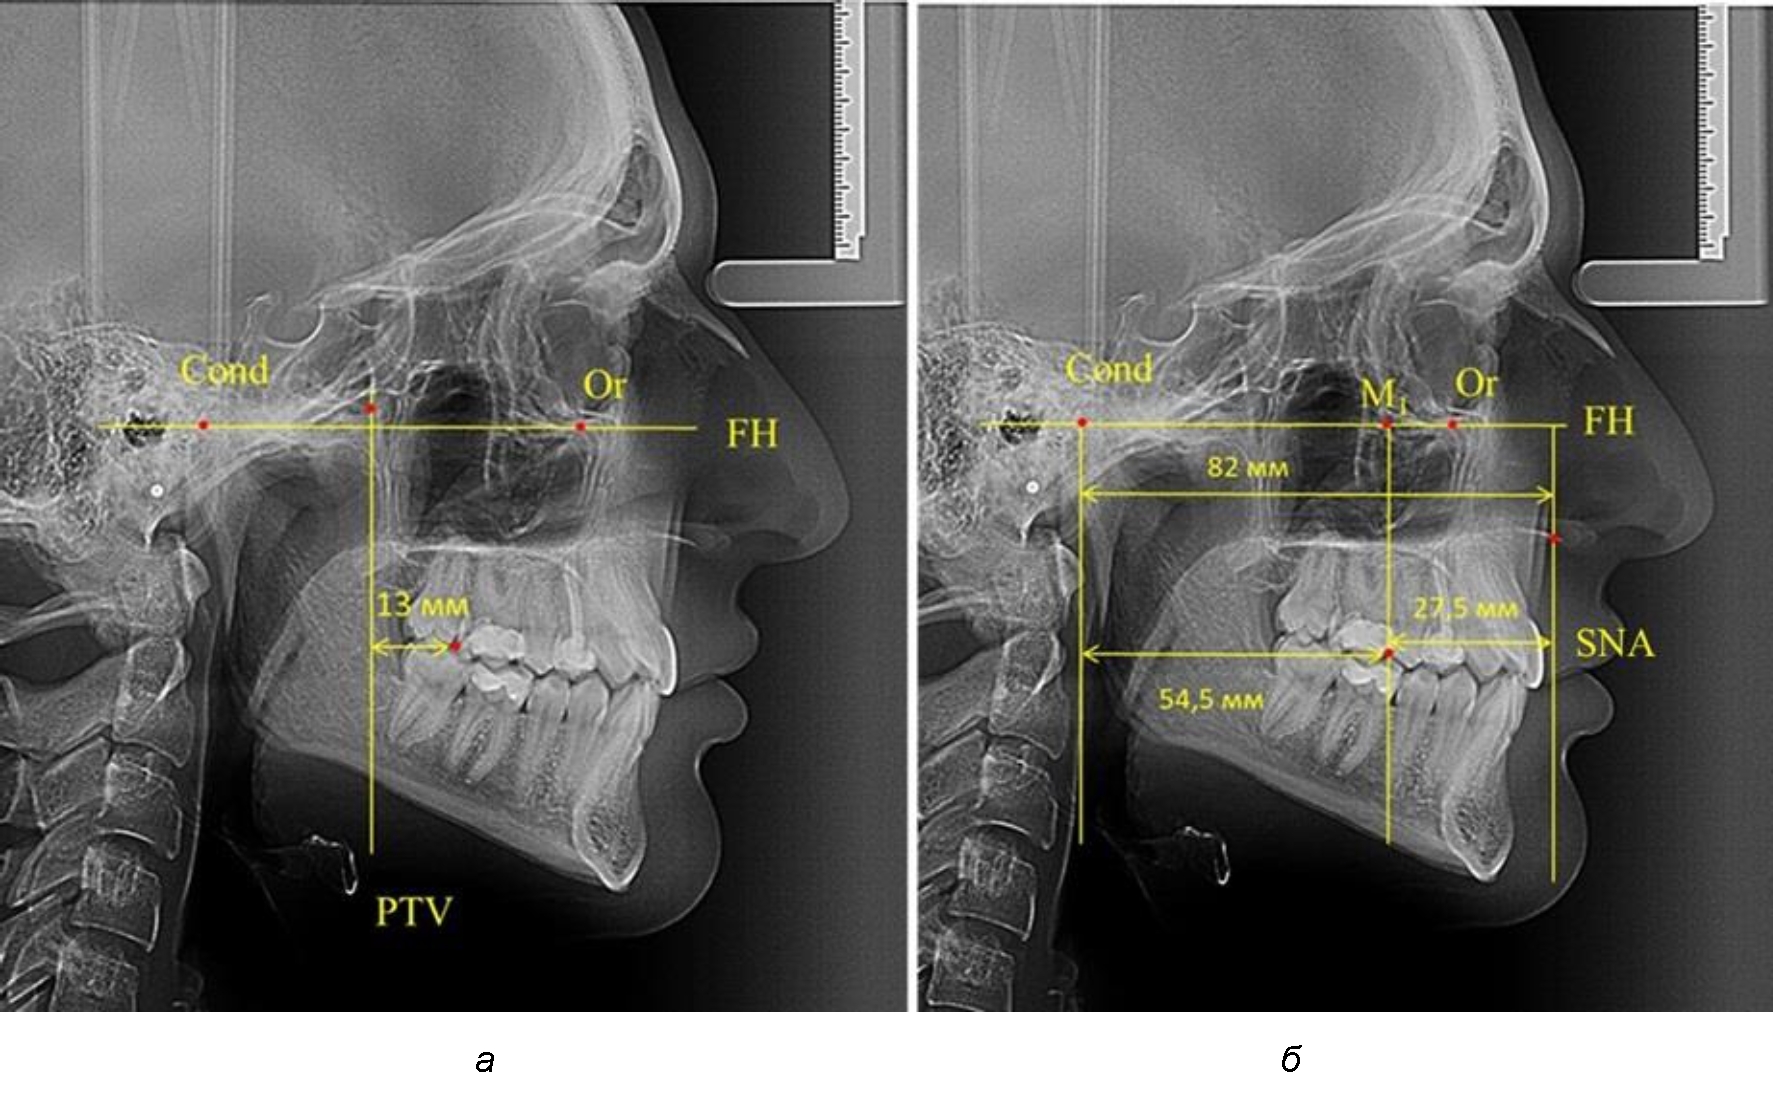

Так, при расстоянии от крыловидной вертикальной плоскости PTV до дистальной поверхности верхнего первого постоянного моляра в 13 мм сагиттальный размер гнатического отдела был 82 мм. При этом отношение кондилярно-спинального расстояния к кондилярно-молярному размеру (54,5) было близким к коэффициенту 1,5, что представлено на рис. 2.

В то же время при увеличенном расстоянии от крыловидной вертикальной плоскости PTV до дистальной поверхности верхнего первого постоянного моляра, равное 23 мм, сагиттальный размер гнатического отдела составил 92 мм. При этом отношение кондилярно-спинального расстояния к кондилярно-молярному размеру (30,5), так же, как и при малых размерах, было близким к коэффициенту 1,5, что представлено на рис. 3.

Рис. 2. Особенности положения первых моляров по R. E. McDonald (а) и по предложенному методу (б) при уменьшенном молярно-крыловидном расстоянии

Рис. 3. Особенности положения первых моляров по R. E. McDonald (а) и по предложенному методу (б) при увеличенном молярно-крыловидном расстоянии